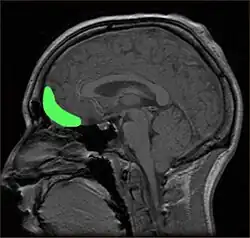

Ilustração da vista lateral do lado direito do cérebro mostrando o lobo frontal, outros lobos do cérebro e o cerebelo

O lobo frontal contém o giro pré-central e o córtex motor primário e, segundo algumas convenções, o córtex orbitofrontal. Essas três áreas estão representadas nos hemisférios cerebrais esquerdo e direito. O giro pré-central ou córtex motor primário é responsável pelo planejamento, iniciação e controle dos movimentos motores finos dorsolaterais de cada hemisfério.[16] A parte dorsolateral do lobo frontal é responsável pelo planejamento, formação de estratégias e outras funções executivas. O córtex pré-frontal no hemisfério esquerdo está envolvido com a memória verbal, enquanto o córtex pré-frontal no hemisfério direito está envolvido com a memória espacial. A região do opérculo frontal esquerdo do córtex pré-frontal, ou área de Broca, é responsável pela linguagem expressiva, ou seja, pela produção da linguagem. O córtex orbitofrontal está relacionado à inibição de respostas, ao controle de impulsos e ao comportamento social.[4]